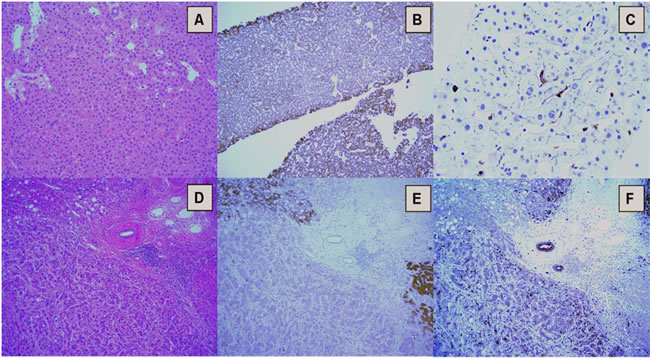

Extensive neovascularization process and sinusoids capillarization could be detected by immunohistochemical staining with endothelial marker CD34 (Figure 1A-B) and the Actin Smooth Muscle antigen (SMA) for muscolarized unpaired arteries. Immunostaining for cytokeratins CK7/19 depicts the ductular reaction, which takes place around nonmalignant nodules: absence of staining could help to identify stromal invasion of well-differentiated malignant hepatocytes into portal tracts. Finally, the overexpression of three specific immunomarkers (Glypican 3- GPC3; Heat Shock protein 70- HSP70; Glutamine synthetase – GS) has been recognized to selectively label small and early HCC as compared to non-malignant counterparts (Table 1) [15, 16]. In the appropriate clinico-pathological context, the finding of 2 unequivocal positive immunomarker (out of 3 among GPC3, HSP70, and GS) can detect early HCC with a sensitivity of 72% and a specificity of 100% [15]. Because of the wide spectrum of histologic appearance of HCC, the differential diagnosis between HCC and other tumors involving the liver can be challenging. Secondary carcinomas may be difficult to assign to their origin but an appropriate immunohistochemical panel (Hep Par 1, pCEA, AFP, CD10, CKs 7, 8/18, 19, 20) may be very helpful to distinguish between primary and metastatic tumors (Table 1) (Figures 1, 2 and 3)[15, 16, 17]

Figure 1: A. Well-differentiated hepatocellular carcinoma, showing a trabecular pattern (Hematoxylin & eosin). B. CD34 immunostaining highlights capillarization of sinusoids, with complete staining around vessel wall. C. CD10 immunostaining shows a peculiar canalicular pattern in HCC. D. Well-moderately differentiated cholangiocarcinoma growing in a trabecular pattern, similar to HCC (Hematoxylin & eosin). E. Strong and diffuse positivity for CK7. F. Strong and diffuse positivity for CK19.

Microscopically, some CCA grow in a cord-like pattern reminiscent of the trabeculae of HCC. The cords are always separated by a connective tissue stroma rather than by sinusoids; canaliculi and bile are also absent (Figure 1D). Immunohistochemistry could be of aid in the differential diagnosis, as almost all CCA are diffusely positive for cytokeratin 7 and 19 (Figure 1E and 1F, respectively), whereas only a few cases of HCC are positive. The hepatocyte antigen (Hep Par 1) is expressed by HCC but not by CCA.